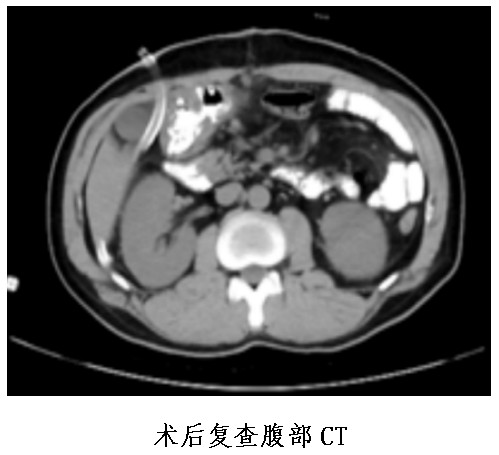

患者因體檢時(shí)發(fā)現(xiàn)肝功能異常后到市中心醫(yī)院消化內(nèi)科住院,進(jìn)行腹部CT發(fā)現(xiàn)胃底及胃體小彎側(cè)局部胃壁結(jié)節(jié)樣增厚、伴胃小網(wǎng)膜囊內(nèi)多發(fā)稍大淋巴結(jié)。超聲胃鏡檢查發(fā)現(xiàn)胃部有多發(fā)隆起病變。病理檢查結(jié)果提示為神經(jīng)內(nèi)分泌瘤。為尋求手術(shù)治療,患者于1月4日轉(zhuǎn)入胃腸外科。

普外中心主任兼胃腸外科主任譚曙光組織醫(yī)師團(tuán)隊(duì)就患者治療方案進(jìn)行討論,認(rèn)為該名胃體神經(jīng)內(nèi)分泌瘤患者,符合手術(shù)指征。經(jīng)過(guò)反復(fù)評(píng)估并與患者本人及家屬溝通,最終譚曙光醫(yī)師團(tuán)隊(duì)決定摒棄傳統(tǒng)的胃切除術(shù),選擇腹腔鏡根治性近端胃切除+D2淋巴結(jié)清掃及雙通道吻合(食道空腸over-Lap吻合及空腸遠(yuǎn)端胃吻合)術(shù),有效減少了反流性食道炎等術(shù)后并發(fā)癥的發(fā)生。1月9日,患者完成了手術(shù),術(shù)后恢復(fù)順利并于22日出院。